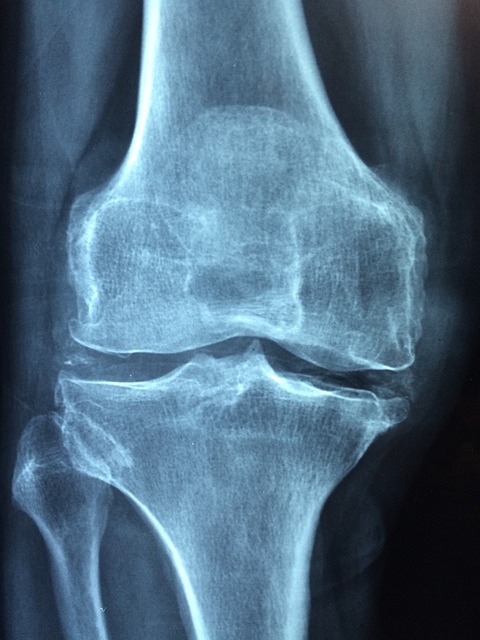

골다공증(Osteoporosis)은 뼈의 밀도와 강도가 감소하여 쉽게 골절되는 만성 대사 질환으로, 특히 폐경 이후 여성과 고령자에게 흔히 발생합니다. 겉으로 드러나지 않는 '조용한 질환'이지만, 한번 발생하면 회복이 어려워 삶의 질에 치명적인 영향을 미칩니다. 본 글에서는 골다공증의 주요 원인, 증상 및 일상에서의 고통, 그리고 효과적인 예방 전략까지 심층적으로 분석합니다.

골다공증의 핵심 원인은 뼈 재형성 과정의 불균형입니다. 정상적인 신체에서는 뼈가 파괴되는 과정(골흡수)과 새로 형성되는 과정(골형성)이 균형을 이루는데, 나이가 들수록 이 균형이 깨져 골흡수가 우세해집니다.

골다공증의 가장 심각한 결과는 골절이며, 이는 단순한 뼈 부상이 아닌 생활 기능 상실과 심리적 위축으로 이어집니다. 특히 고관절이나 척추 골절은 고령자에게 생명을 위협하는 수준입니다.

외형 변화(구부정한 자세, 키 감소)는 특히 여성 환자들에게 심리적인 스트레스 요인이 될 수 있습니다. 실제 통계에 따르면 고관절 골절 환자의 20~25%는 1년 이내 사망하며, 절반 이상이 영구적으로 돌아오지 않습니다. 골다공증은 요즘 젊은 층에서도 많이 발생되곤 합니다. 서구문화적인 식생활들과 부족한 운동량과 햇빛마저 받지 않는 결핍된 생활들로 인해 발생 수가 증가하고 있습니다. 꼭 노화로 인한 문제가 아닙니다.